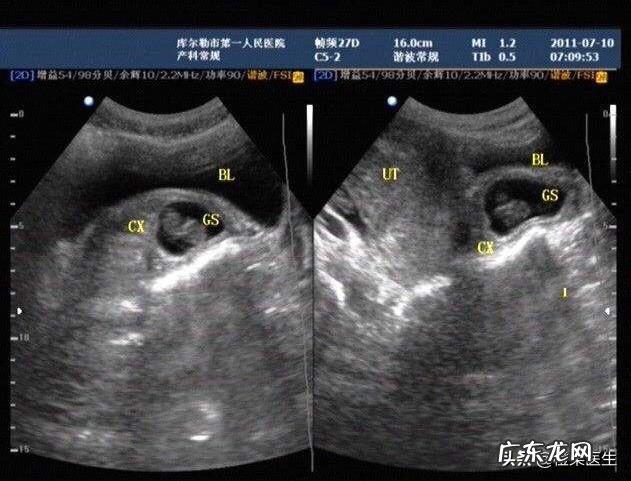

你好,非常高兴为你解答问题,胎盘的成熟度共分四ji:Oji,1ji,2ji和3ji 。

1ji标志胎盘基本成熟;2ji标志胎盘已经成熟;3ji标志胎盘已开始衰老,由于钙化和纤维素沉着,使胎盘输送氧气及营养物质的能力降低 。一般妊娠中期(12—28周)胎盘0ji;妊娠晚期(30—32周)胎盘Ⅰji;36周以后胎盘Ⅱji(比较成熟) 。

一般来说,孕32周以后胎盘成熟度2ji,标志着胎盘已经开始成熟 。但是胎盘是可以提前成熟的,胎盘老化实际上不是一个很科学的问题,因为胎盘和孩子一样,有一个发生、成长、发育、成熟这样的过程,到了三ji很多人认为老化了,其实从35周以后三ji只保证它的成熟,并不是说它的老化,胎盘功能的好坏根据很多的检查,比如说羊水的多少,另外胎心的监护怎么样,一些生化的检测,也能知道胎盘功能是不是好 。同时机器的分辨率和医生观看的因素也是要考虑的 。

胎盘提前老化,本身不是一个标准的医学概念,象妊娠30~35周胎盘即出现胎盘2~3ji钙化,只能说明胎盘成熟度,与胎盘功能不一定有必然的联系 。胎盘功能减退,多是过期妊娠,或孕妈妈存在妊娠合并症,如妊娠高血压、糖尿病等,都会导致胎盘血液供应减少,加速胎盘老化 。而且妇产科医生不但看胎盘的分ji,更重要的是看羊水,只要羊水正常,胎儿就没有大风险 。